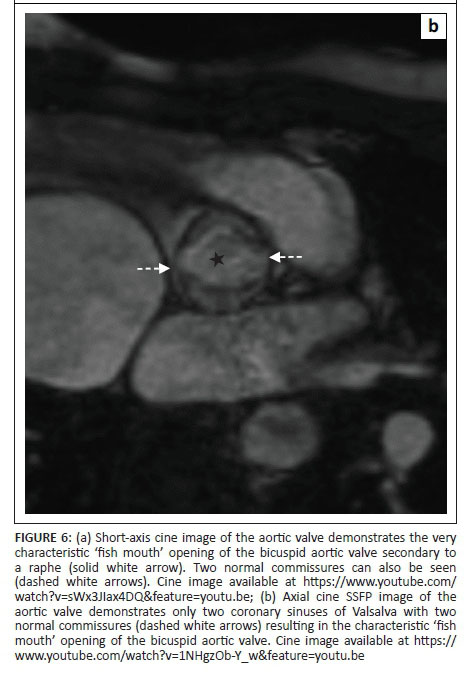

The most common leaflet abnormality of the aortic valve is a bicuspid aortic valve. The most common form of the bicuspid aortic valve is that of a valve with one raphe (Figure 6a) which is the result of fusion of two adjacent cusps.4 On rare occasions, the bicuspid valve is secondary to a bisinus valve, with only two sinuses of Valsalva and two cusps. No raphes are seen in these cases but the abnormality still results in the same characteristic 'fish mouth' opening of the valve (Figure 6b).